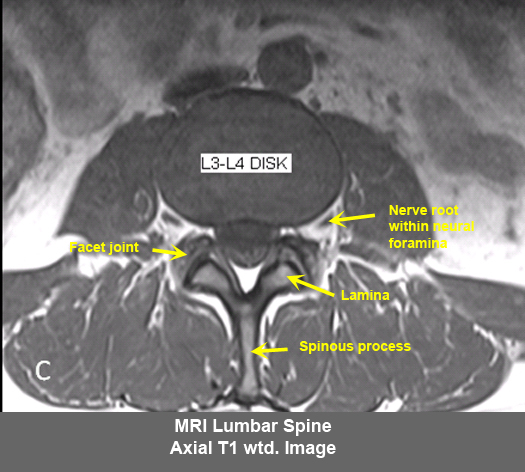

MR Brain and Spine